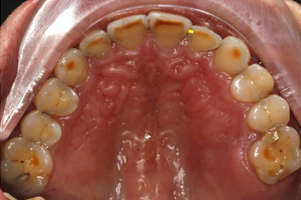

Porcelain onlays: 16, 15, 26, 25

Porcelain veneerlays: 14, 24, 36, 35, 34, 44, 45, 46

Porcelain crowns: 13, 23

Porcelain veneers: 12, 11, 21, 22, 33, 32, 31, 41, 42, 43